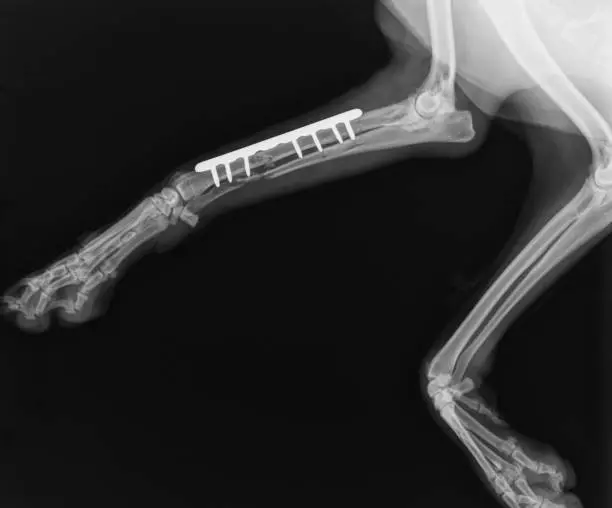

A clina veterinária raio X é um exame de imagem fundamental na medicina veterinária, pois permite visualizar a estrutura óssea dos animais, auxiliando na identificação de possíveis lesões, fraturas, deslocamentos e outras alterações.

Na Zoozotic, os exames de raio x são realizados com equipamentos modernos e seguros, garantindo precisão nos diagnósticos e contribuindo para a definição de tratamentos eficazes.

Benefícios do Exame de Raio X na Saúde dos Pets

A clínica veterinária raio x é uma ferramenta essencial para o diagnóstico e tratamento de diversas condições de saúde em animais de estimação.

Através desse exame, os veterinários podem identificar problemas ortopédicos, doenças respiratórias, câncer, entre outras enfermidades, possibilitando intervenções precoces e eficazes para garantir o bem-estar dos pets.